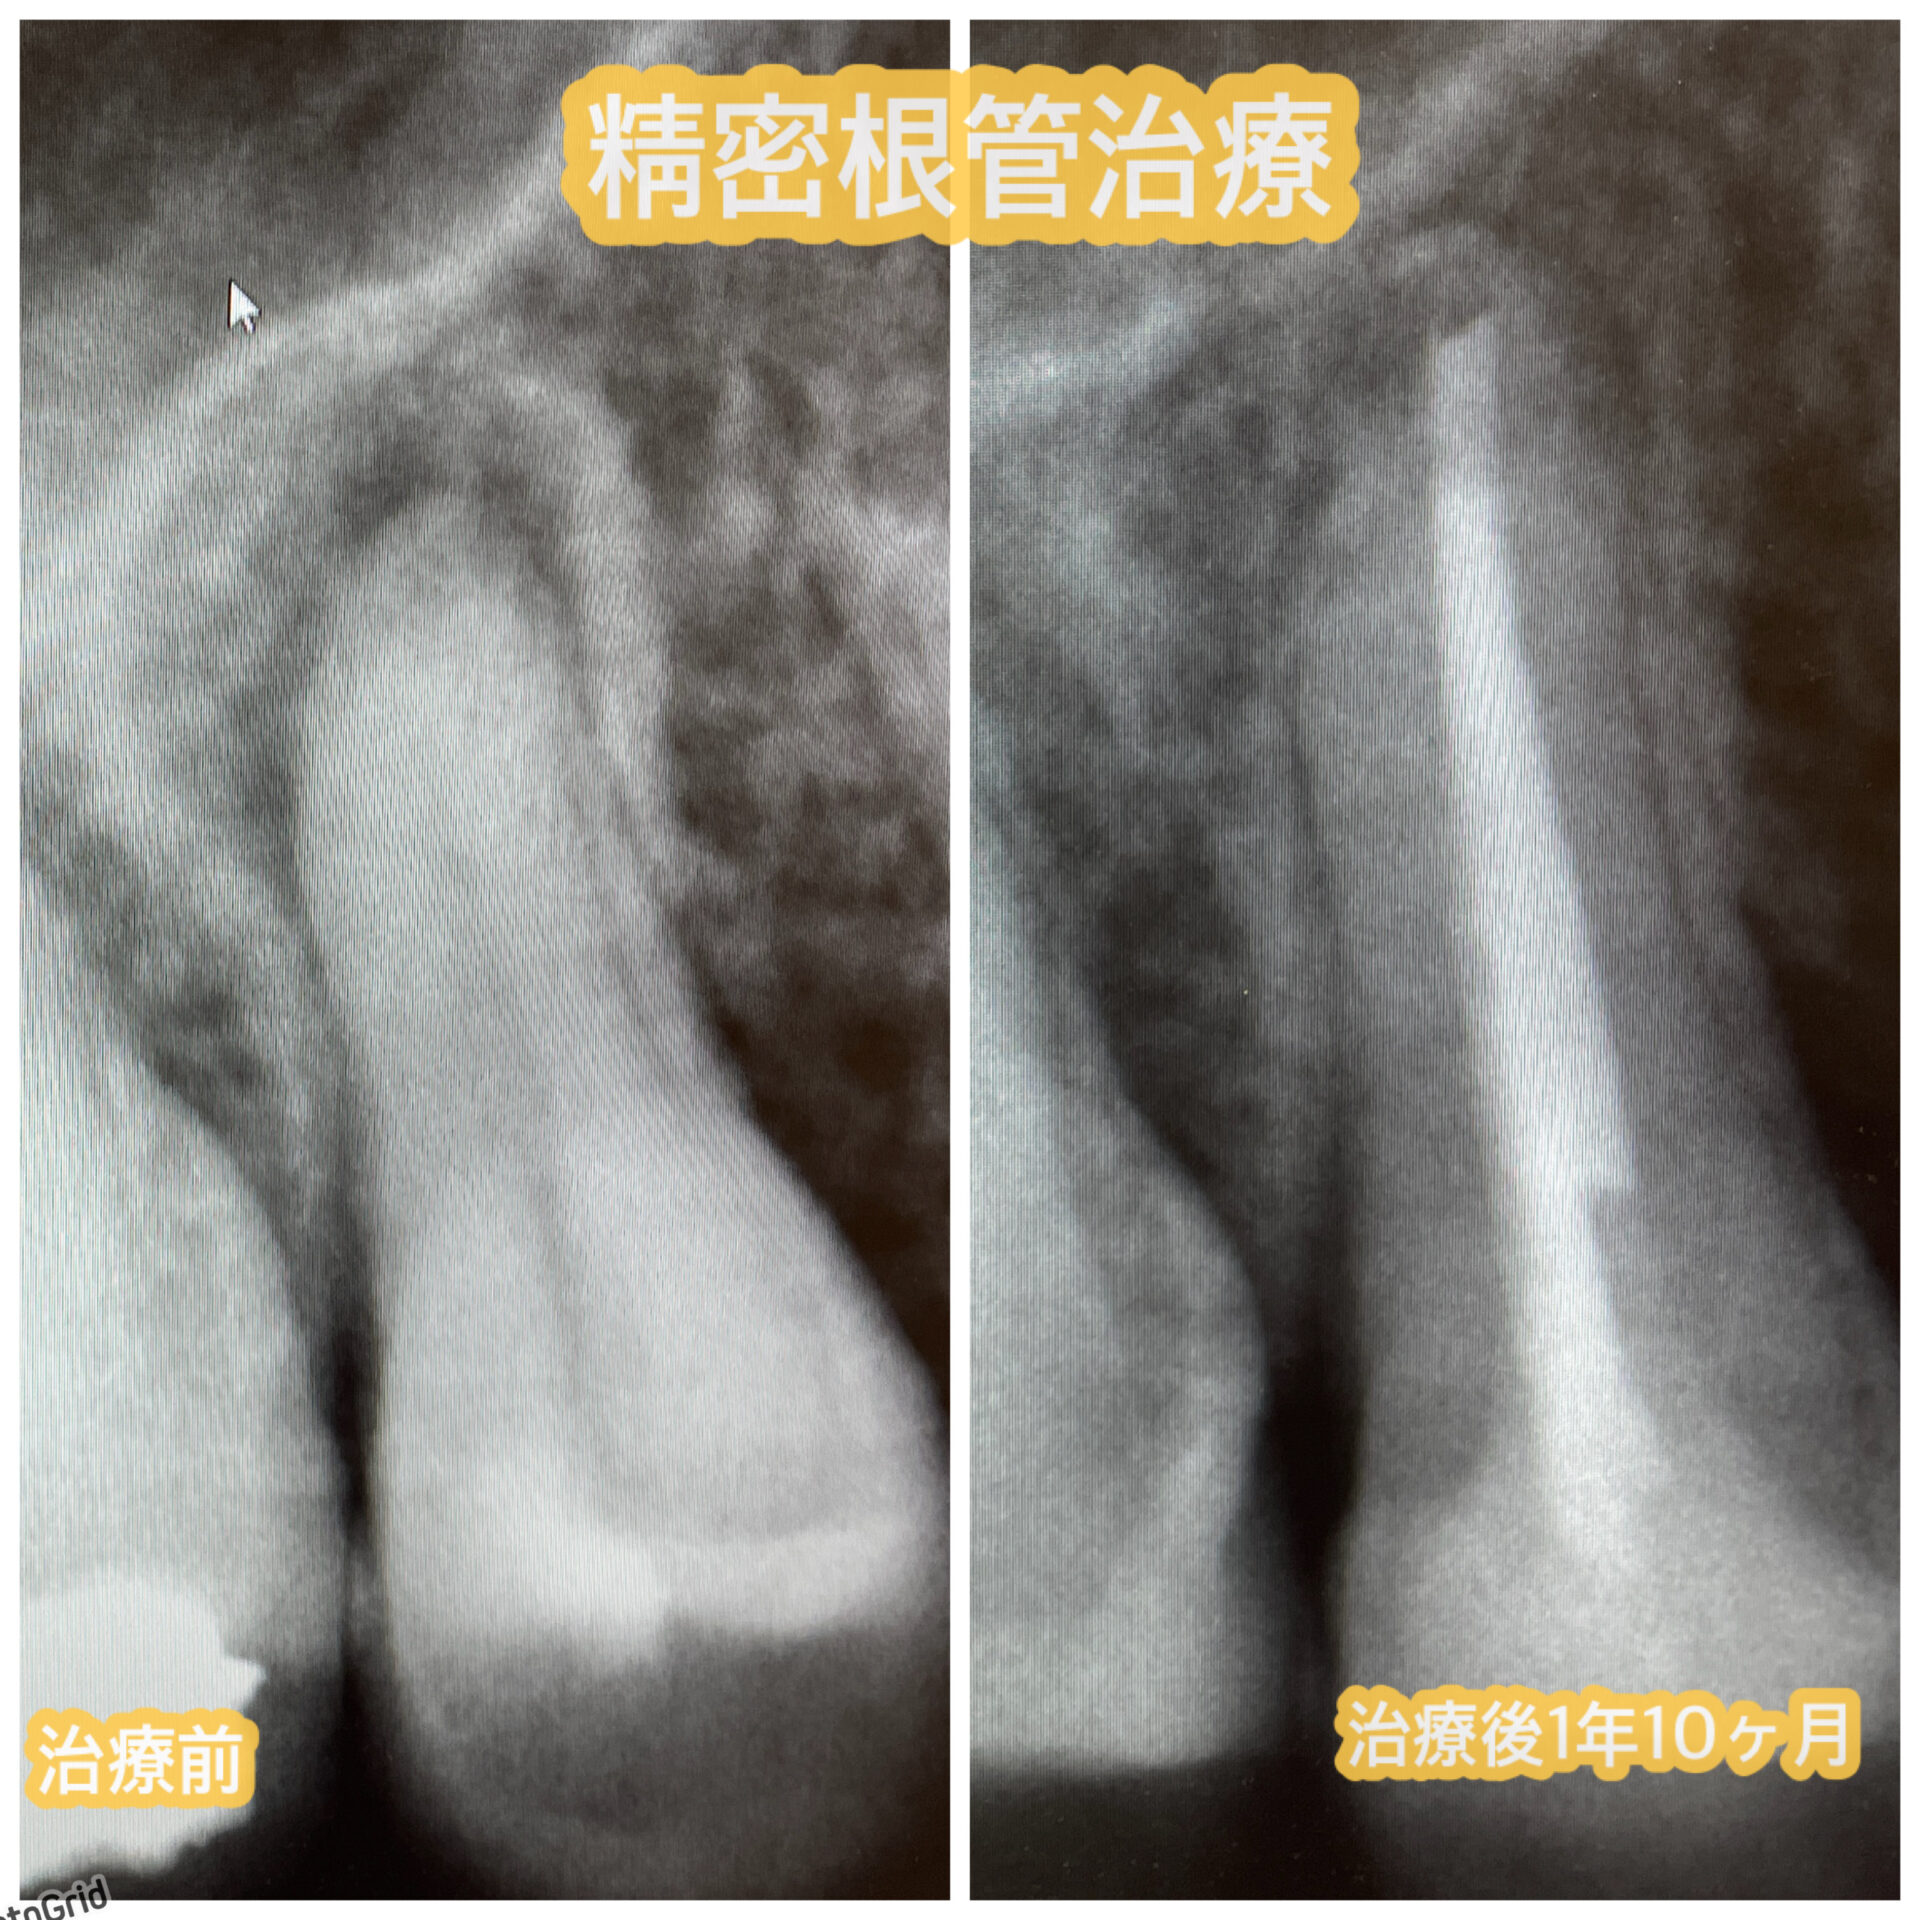

40代女性他院セラミックの修正治療

モニター様ご紹介 20年ほど前に他院で受けたセラミック治療をした歯のお痛みがあるのと、治した歯の周囲が黒く目立つので改善したいとご相談くださいました。当院に通ってくださっている方からのご紹介です。 初診時の状態 他院セラミックの上の歯茎が痛いという症状があったのでレントゲン撮影とCT撮影をしています。前歯の根の先に黒い影が見えます。これは根の先に膿が溜まって …